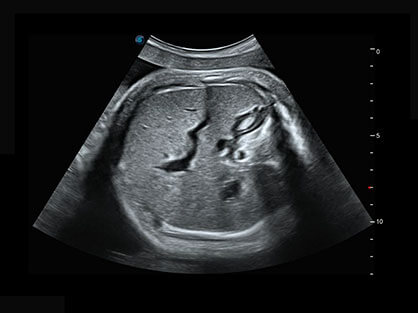

0.5mm厚度的薄层切片显像,可清晰显示微小病灶的连续断面。

自动获取标准切面,自动完成测量,帮助医生快速完成检查,同时提升测量准确性。